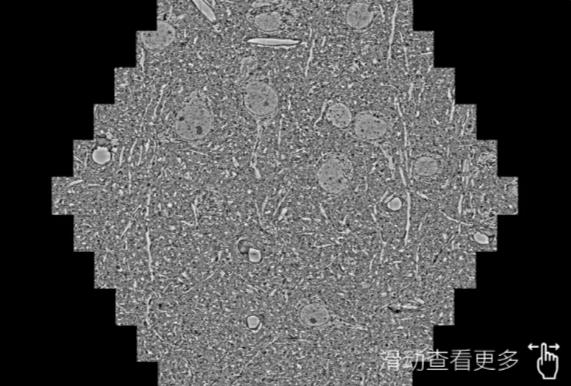

鼠脑切片。左图使用蓟州蔡司蓟州扫描电镜MultiSEM706对165μmx143pm面积区域成像,耗时仅需1.5秒。右图为鼠脑切片中30μm区域放大效果。样品由芝加哥大学B.Kasthuri提供。

使用蔡司高速蓟州扫描电镜MultiSEM对1mm²人脑皮层组织进行高分辨成像,并对其中的各种细胞结构进行三维重构分析。左图展示了2x3mm²组织平面中锥体神经元的三维重构效果。右图显示了局部体积神经元三维重构。图像由哈佛大学chtman实验室提供,渲染图由D. Berger 制作。